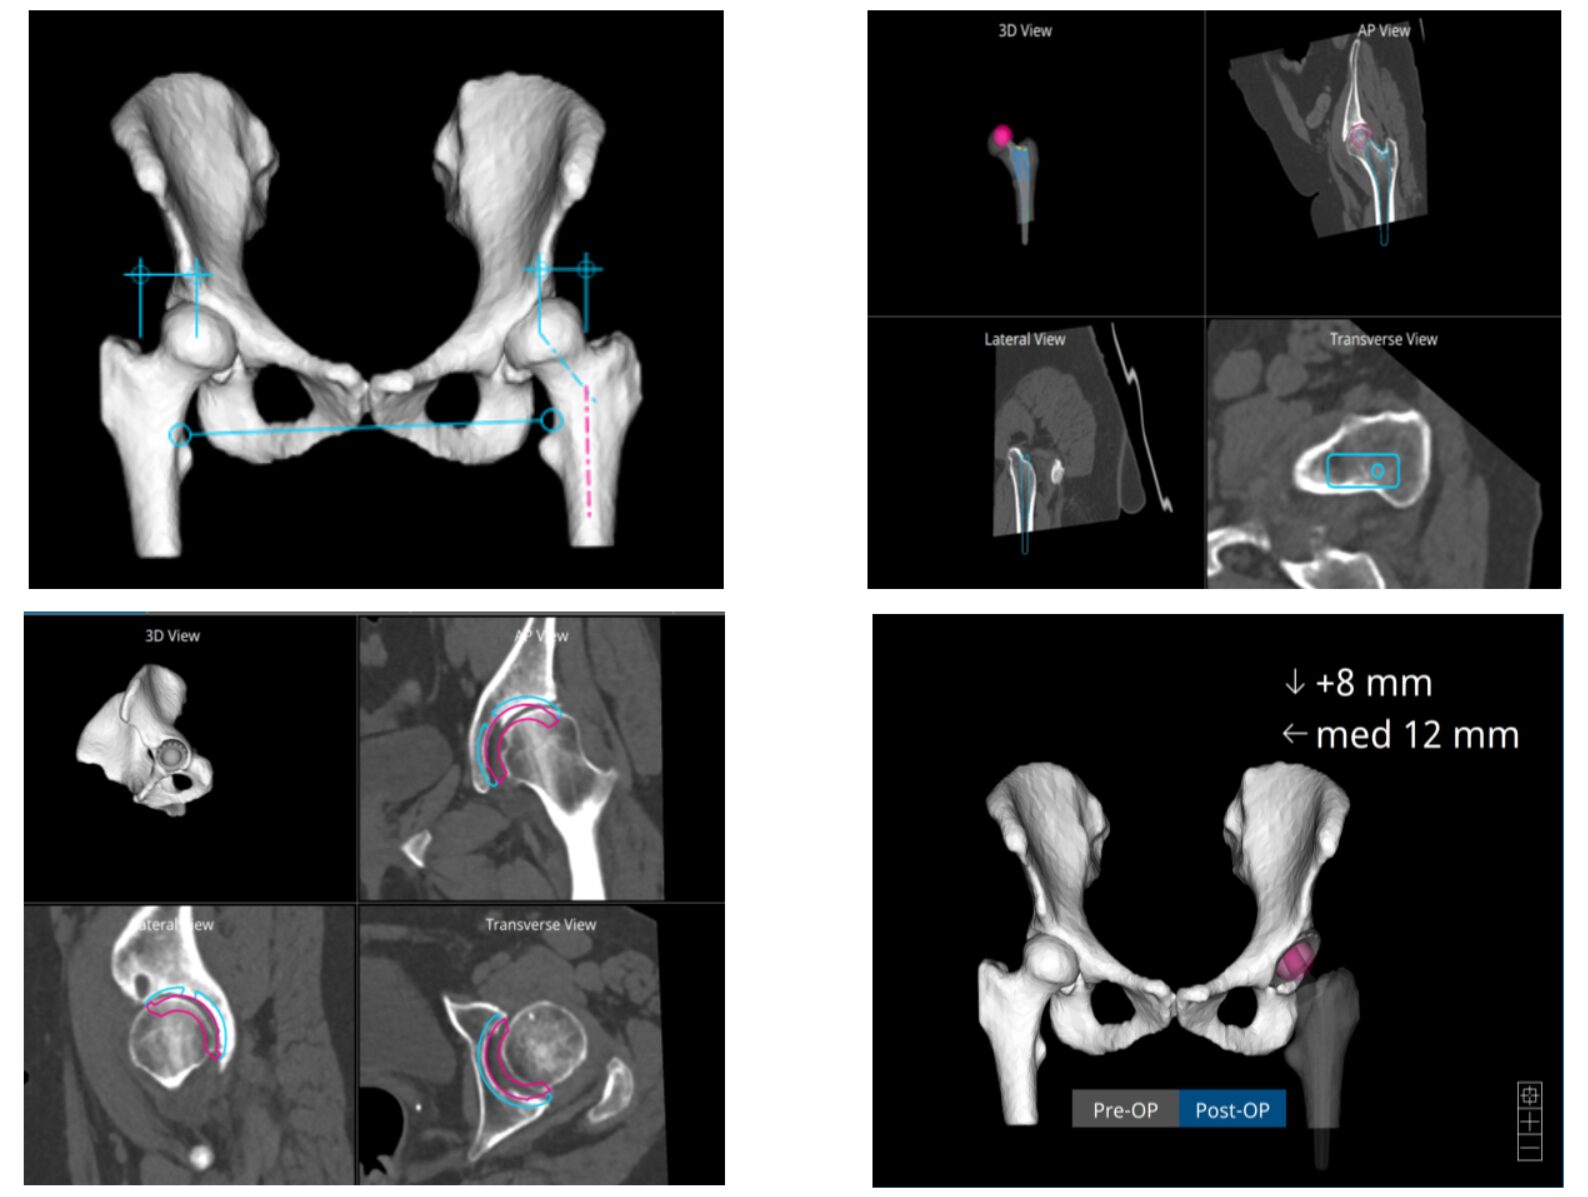

Στην εικόνα 6 απεικονίζεται η ακτινογραφία ασθενούς, από το αρχείο μας, με προχωρημένη αρθρίτιτδα και των δύο ισχίων. (Ο ασθενής υποβλήθηκε την ίδια μέρα σε ταυτόχρονη αρθροπλαστική AMIS και στα δύο ισχία του)

Στην εικόνα 6 βλέπουμε την προεγχειρητική ακτινογραφία άνδρα 56 ετών που υποβλήθηκε σε ταυτόχρονη αρθροπλαστική AMIS με navigation robotic assistance. Στην εικόνα 21 ο προεγχειρητικός τρισδιάστατος σχεδιασμός, αναλυτικά. Στην εικόνα 22 η πλοήγηση από το σύστημα διεγχειρητικά, με απόλυτη ακρίβεια και το άριστο τελικό ακτινολογικό αποτέλεσμα. Ο ίδιος ασθενής στην επανεξέταση, 24 μέρες μετά την επέμβαση στο ιατρείο.